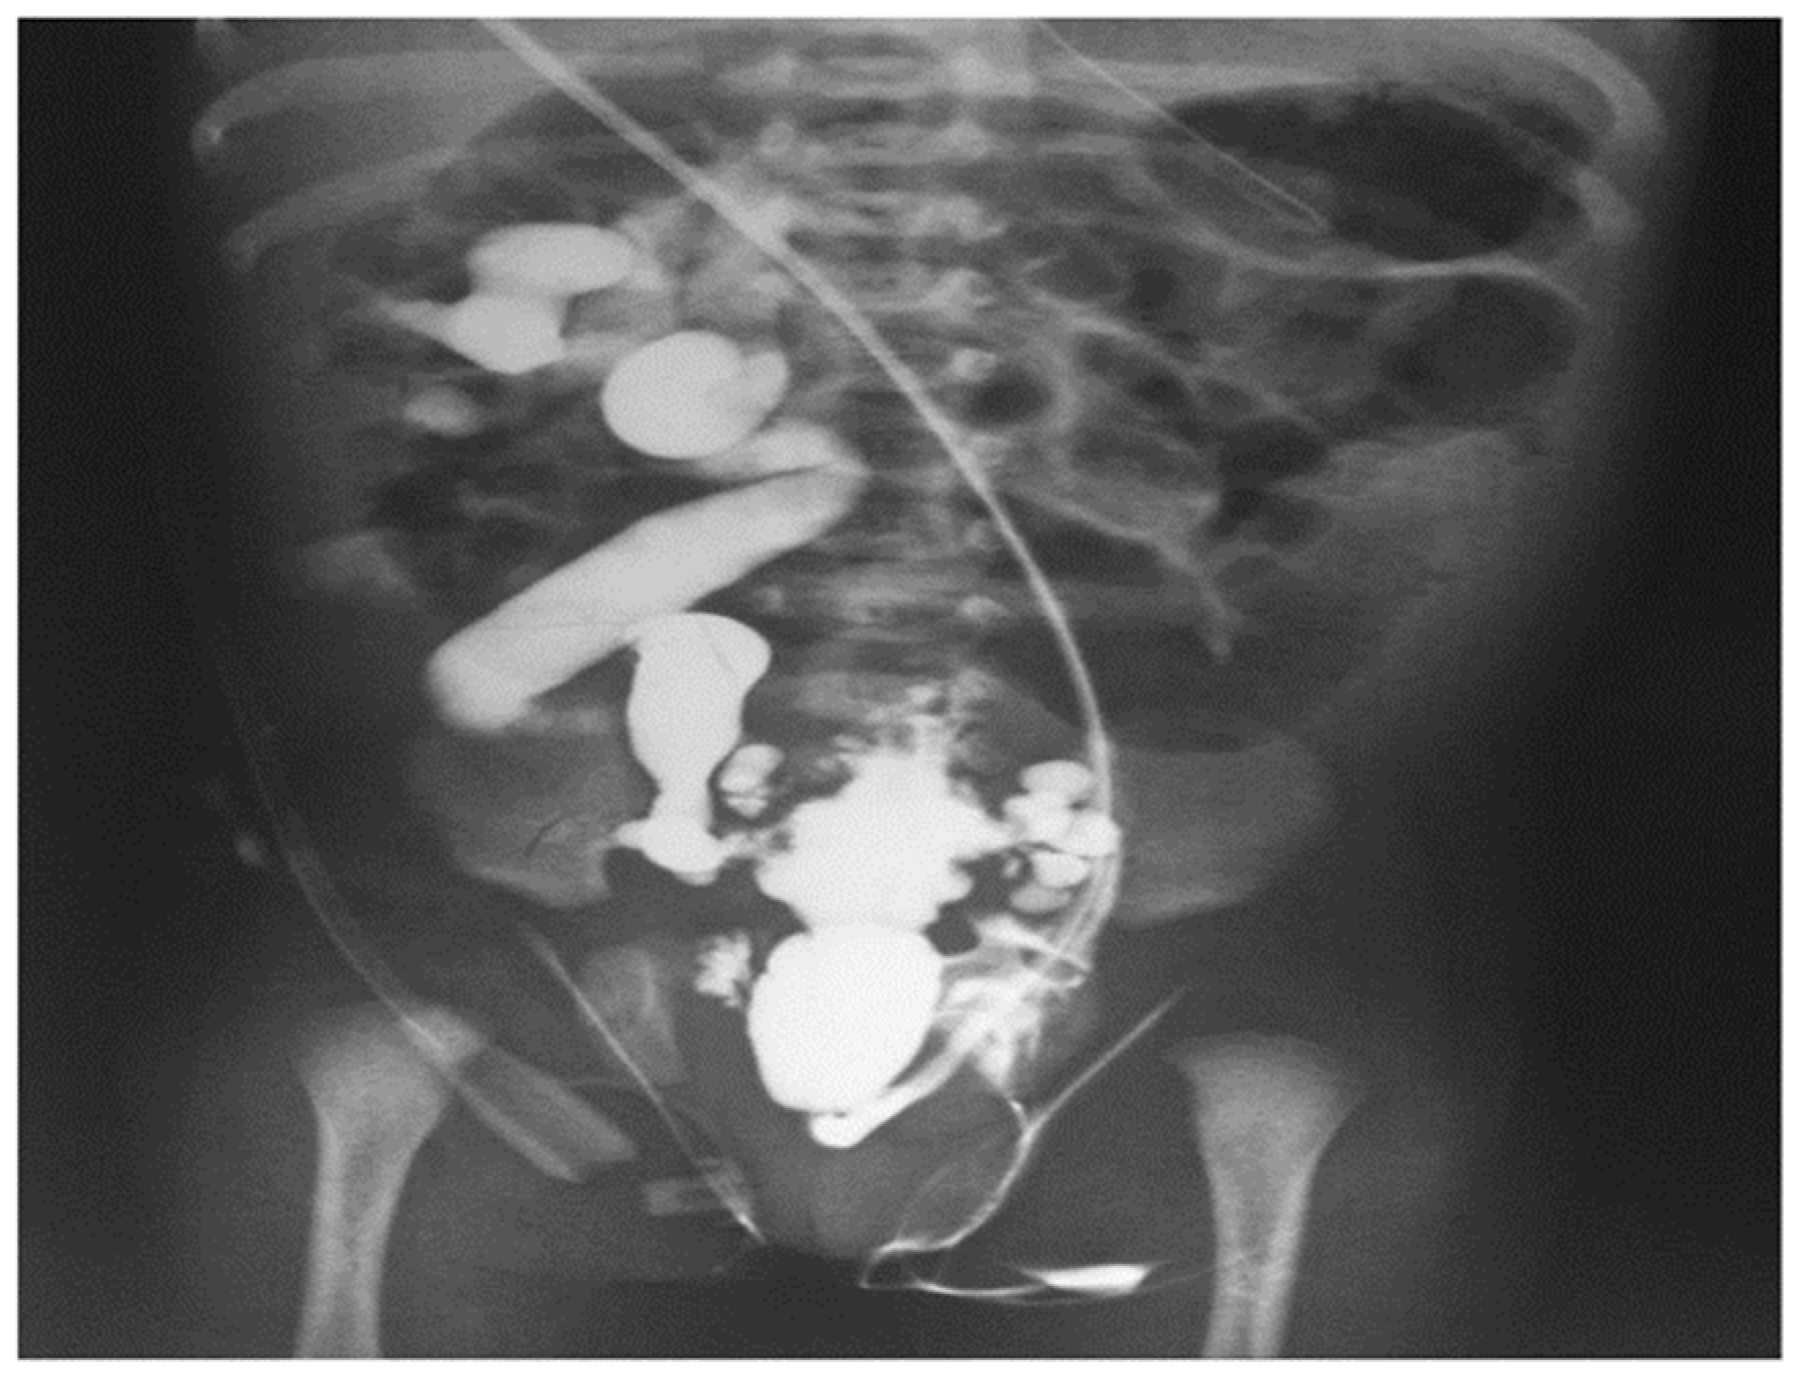

Weaver et al. (2023) [62] emphasized the application of DL to extract characteristics from postnatal kidney ultrasounds that forecast progression to chronic kidney disease (CKD) in children with PUV. At present, assessment of CKD risk relies on the lowest level of creatinine during the initial year of life. Levels below 0.8 mg/dL indicate negligible risk, whereas levels above 1.2 mg/dL indicate increased likelihood of kidney failure. Figure 9 shows that upon examination, a micturating cystourethrogram can confirm the presence of type 1 PUV, in addition to matching abnormalities in the bladder (trabeculation) and upper urinary system.

Figure 9. Micturating cystourethrogram revealing the presence of type 1 PUV together with corresponding alterations in the bladder (trabeculation) and upper urinary system (vesicoureteral reflux) [60].

• Methods of Diagnosis: VCUG is widely recognized as the most reliable method of validating a PUV diagnosis. According to Fishberg et al. (2018) and Kwong et al. (2022), VCUG enables the observation of valvular obstruction, a bladder that is thickened and has trabeculations, diverticuli, and vesicoureteral reflux.